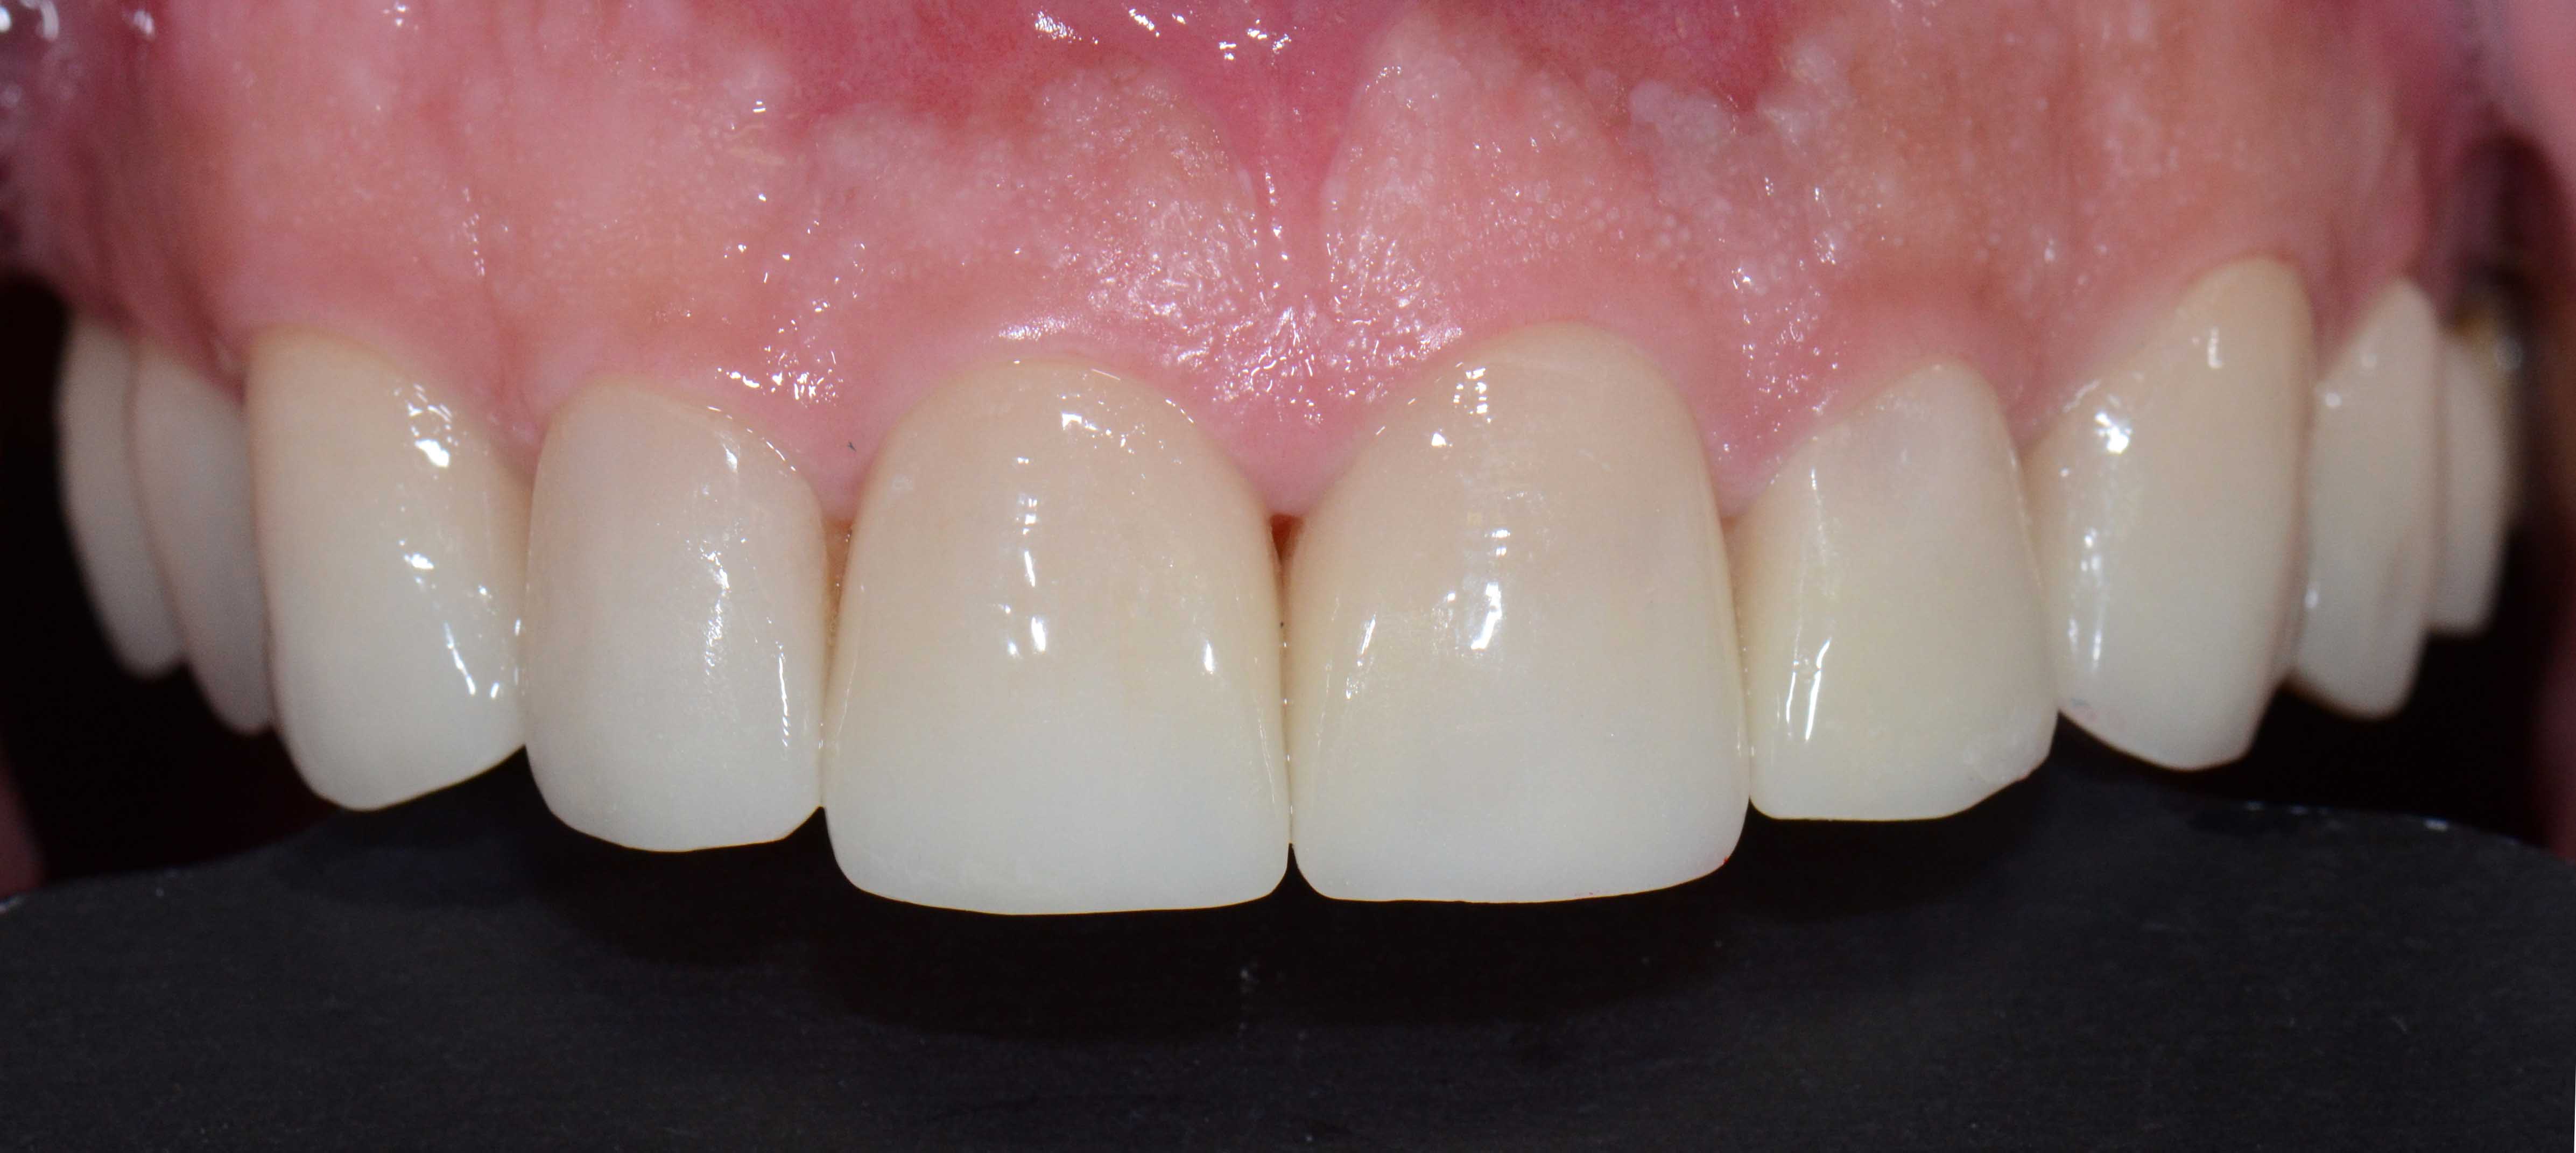

Finalizou-se com colocação de Coroas Cerâmicas.

Reabilitação Estética com Coroas e Facetas Cerâmicas.

Opção por recobrimento dentário com coroas nos dentes mais destruidos e de facetas naqueles menos atingidos evitando desgastes muito agressivos.